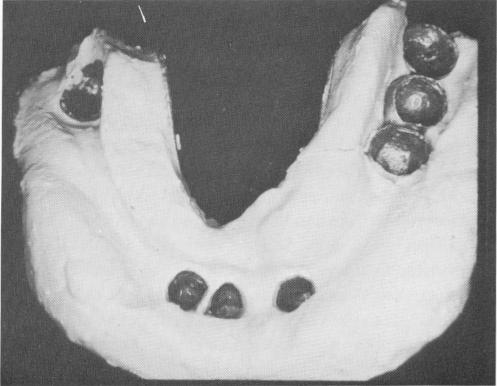

Fig. 15-4. All lower teeth were prepared parallel to each other, without any nerve exposures, and castings were made and fitted over the prepared teeth.

Fig. 15-5. A plaster index picked up all of the mandibular copings.

2 Castings on prepared lower teeth for implant prosthesis placement

3 Plaster index of mandibular coping for implant prosthesis fabrication